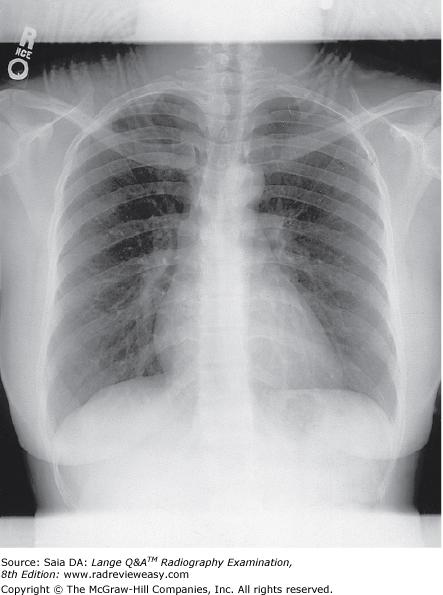

The radiograph seen below illustrates incorrect use of

A collimator

B grid

C AEC

D focal spot

-An upside-down focused grid presents its lead strips in the opposite direction to that of the x-ray beam. This results in severe grid cutoff everywhere except in the central portion of the radiographic image. Severe grid cutoff of chest anatomy can be seen outside the central exposed area. A misaligned collimator would not show such symmetrical loss of receptor exposure, nor would an incorrectly selected AEC photocell. Focal spot is unrelated to receptor exposure.